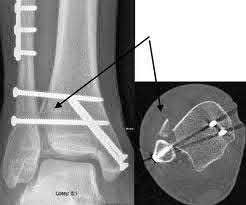

A 25-year-old male sustains an ankle fracture dislocation and undergoes open reduction and internal fixation. He returns to clinic five months following surgery complaining of continued ankle pain and instability with weight bearing. His immediate post-operative AP radiograph is seen in Figure A. Which of the following could have prevented this patient from developing persistent pain?

The patient presents with continued ankle pain and instability following open reduction and internal fixation. The radiograph in figure A demonstrates inadequate restoration of fibular length, likely leading to continued tibiotalar instability.

Illustration A demonstrates fibular malreduction with dislocation of the fibula anterior to the tibial incisura. Illustration B shows a comminuted fibula fracture along with a measurement of length from an intact fibula. The arc from the lateral process of the talus to the peroneal groove of the distal fibula is known as the "dime" sign and should remain unbroken if fibular length has been restored. Illustration C demonstrates the use of a push-pull screw and lamina spreader to regain length intraoperatively for a comminuted fibula fracture.

Chu and Weiner review management of malunions of the distal fibula. The authors state that restoration of fibular length, alignment and rotation leads to reduction of the talus, provides a buttress to talar motion in the setting of an incompetent deltoid, and allows the syndesmotic ligaments to heal at the appropriate tension.